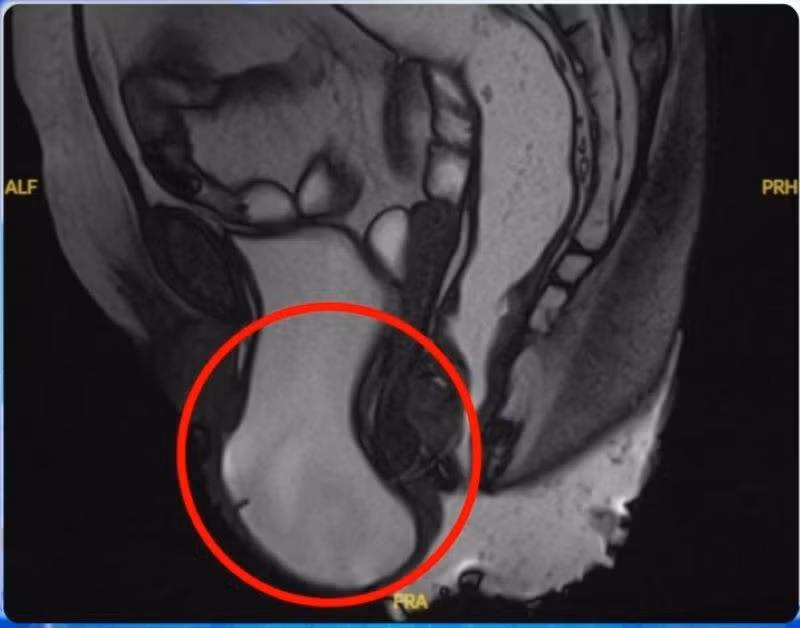

Khi đến khám tại Phòng khám khoa Ngoại Tiết Niệu – Bệnh viện Đa khoa Xuyên Á Long An, bà T. đã được các bác sĩ thăm khám và chụp MRI sàn chậu. Kết quả cho thấy bà mắc sa sàn chậu độ III, sa bàng quang độ III và sa tử cung độ II.

Hình ảnh cận lâm sàng cho thấy bệnh nhân bị sa sàn chậu độ III, sa bàng quang độ III và sa tử cung độ II - Ảnh BVCC